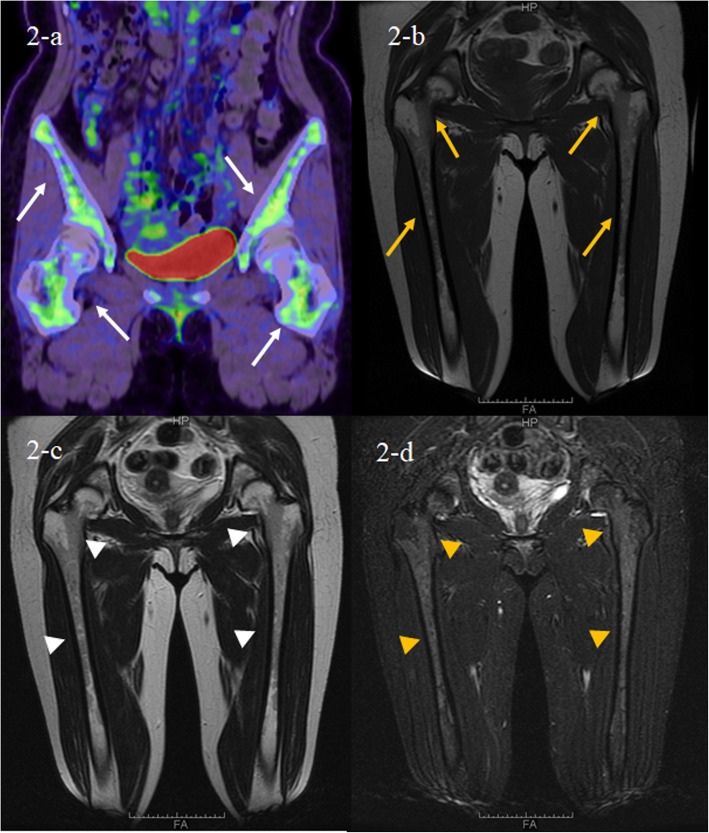

PET/CT showed the diffuse fluorodeoxyglucose (FDG) uptake in the bone marrow of both femoral and pelvic bones (Fig. 2a). MRI of both femurs (Fig. 2c-d) show diffusely abnormal signal in the medullar bone of both femoral bones. Histological findings of the biopsied urticarial lesions showed a neutrophilic urticarial dermatosis demonstrating perivascular and interstitial neutrophilic infiltrations without leukocytoclastic vasculitis (Fig. 3). Based on the urticarial rash, recurrent fever, abnormal bone remodeling with bone pain, and elevated acute phase reactants, SchS was suspected, despite the absence of monoclonal gammopathy. The patient had been treated with high-dose prednisolon, antihistamines, omarizumab, and cyclosporine A; however, she was unresponsive to these various treatments. The observation that she did not respond to any conventional medications indicated the possibility of autoinflammatory diseases. Therefore, written informed consent for gene analysis for autoinflamatory genes was obtained from the patient, and the ethical approval for the study was obtained from the Fukushima Medical University Ethics Committee for this retrospective study (No 2019–188) and in accordance with the Declaration of Helsinki. In order to exclude the mutations in the genes of autoinflammatory diseases, the genetic screening was performed in genomic DNA samples from the patient whole blood under analysis by next-generation sequencing. A panel was created to identify possibly disease-causing mutations in 14 autoinflammation/immune-related genes (MEFV, TNFRSF1A,NLRP3,NLRP12,VK,PLCG2,NOD2,TMEM173,PSMB8,PSMA3,PSMB4,PSMB9,POMP,NLRC4). However, neither mutation nor rare variant was found in these genes (data not shown). Despite the lack of diagnostic criteria for the typical SchS (absence of monoclonal gammopathy) and CAPS (absence of NLRP3 mutation or somatic mosaicism), we did not exclude the possibility of antoinflammatory diseases including SchS. Neutrophilic urticarial with systemic inflammation (NUSI) characterized by urticarial skin lesions with neutrophilic infiltration likely mediate by IL-1 [7]. The differential diagnosis of NUSI should be considered in this case with antihistamine or immunosuppressant-resistant urticaria with systemic inflammation [7]. Exclusion of known inflammatory diseases is necessary for the diagnosis of NUSI [7]. Although inflammatory arthritis could be associated with NUSI [7], bone pain with bone remodeling, one of the clinical findings of SchS, may not be present with NUSI. The lack of monoclonal gammopathy does not necessarily deny SchS because monoclonal gammopathy may not be present at disease onset [8]. She fulfilled the diagnostic criteria for SchS except monoclonal gammopathy.

Fig. 2.

FDG-PET/CT and MRI findings. The FDC-PET/CT findings of femurs demonstrate increased 18FDG uptake in the bone marrow at the pelvis and femurs (a, white arrows). The MRI findings of femurs demonstrates low signal intensity on the T1-weighted image (b, yellow arrows) and T2-weighte image (c, white arrowheads) whereas high signal intensity on the STIR image (d, yellow arrowheads). 18FDG = fluorine-18-fluro-deoxyglucose, PET/CT = positron emission tomography/computed tomography, MRI = magnetic resonance imaging, STIR = short T1 inversion recovery

Schnitzler syndrome is a rare autoinflammatory disease with typical skin manifestations [1]. The presence of the typical skin lesion of an urticarial dermatosis and monoclonal gammaopathy by IgM are essential for the disease diagnosis [11]. Our case presented with SchS resembling urticarial skin lesions characterized by perivascular and interstitial neutrophilic infiltrations without vasculitis histologically. Recent imaging study suggested the abnormal bone remodeling involving of long bones in SchS [12]. In our case, abnormal FDG uptake in both proximal femurs in PET/CT and high signals in MRI examination suggesting the high bone remodeling on bone pain lesions. Despite these clinical manifestations resembling SchS, monoclonal gammaopathy was not observed in the present case.